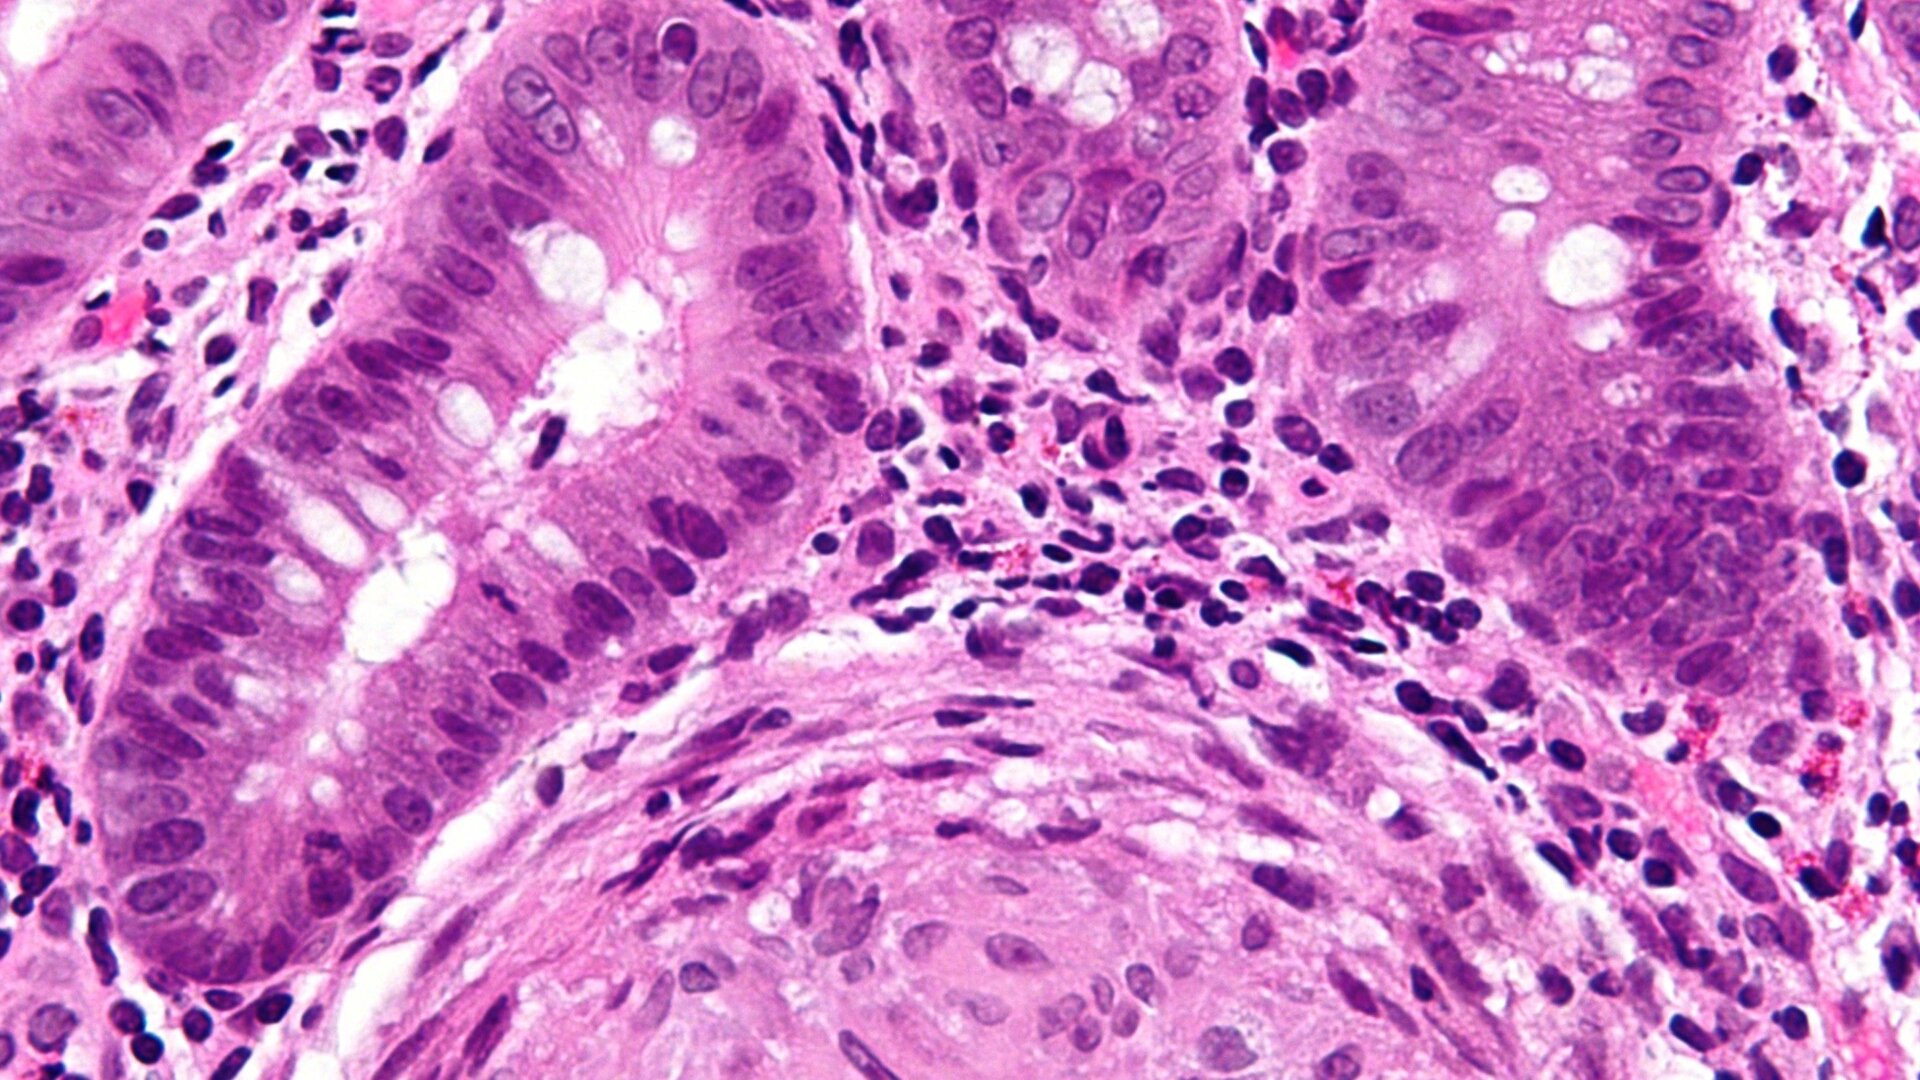

The scientists studied mice that were made to develop Crohn’s-like symptoms as well as biopsied samples of gut tissue from people diagnosed with Crohn’s. Across both groups, they found an abundance of D. hansenii around wounded or inflamed tissue, but not in samples taken from healthy people or in the uninflamed tissue of Crohn’s patients.

They found the fungi in all of the seven samples taken from a group of Crohn’s patients, for instance, but in only one of the 10 healthy controls used as comparison. They also found evidence that this yeast was directly connected to the slow healing of gut wounds in mice. And when they took samples of the fungi from a Crohn’s patient or diseased mice and gave it to a new group of healthy mice, the mice’s ability to heal gut wounds became worse. This effect was then reversed when mice were given antifungal treatment.